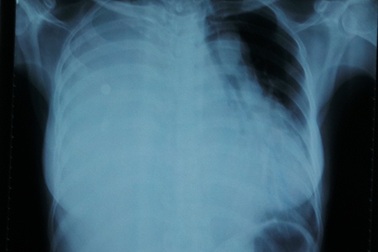

Chẻ xương ức, bóc khối u “hiếm” chiếm trọn lồng ngựcBị khối u nặng 4,5kg đè xẹp phổi, xô lệch tim nhưng người phụ nữ 41 tuổi vẫn mang thai và vượt cạn thành công. Các bác sĩ phải chẻ xương ức, mở lồng ngực mới bóc được khối u ra ngoài, đây là trường hợp rất hiếm gặp trong y văn.